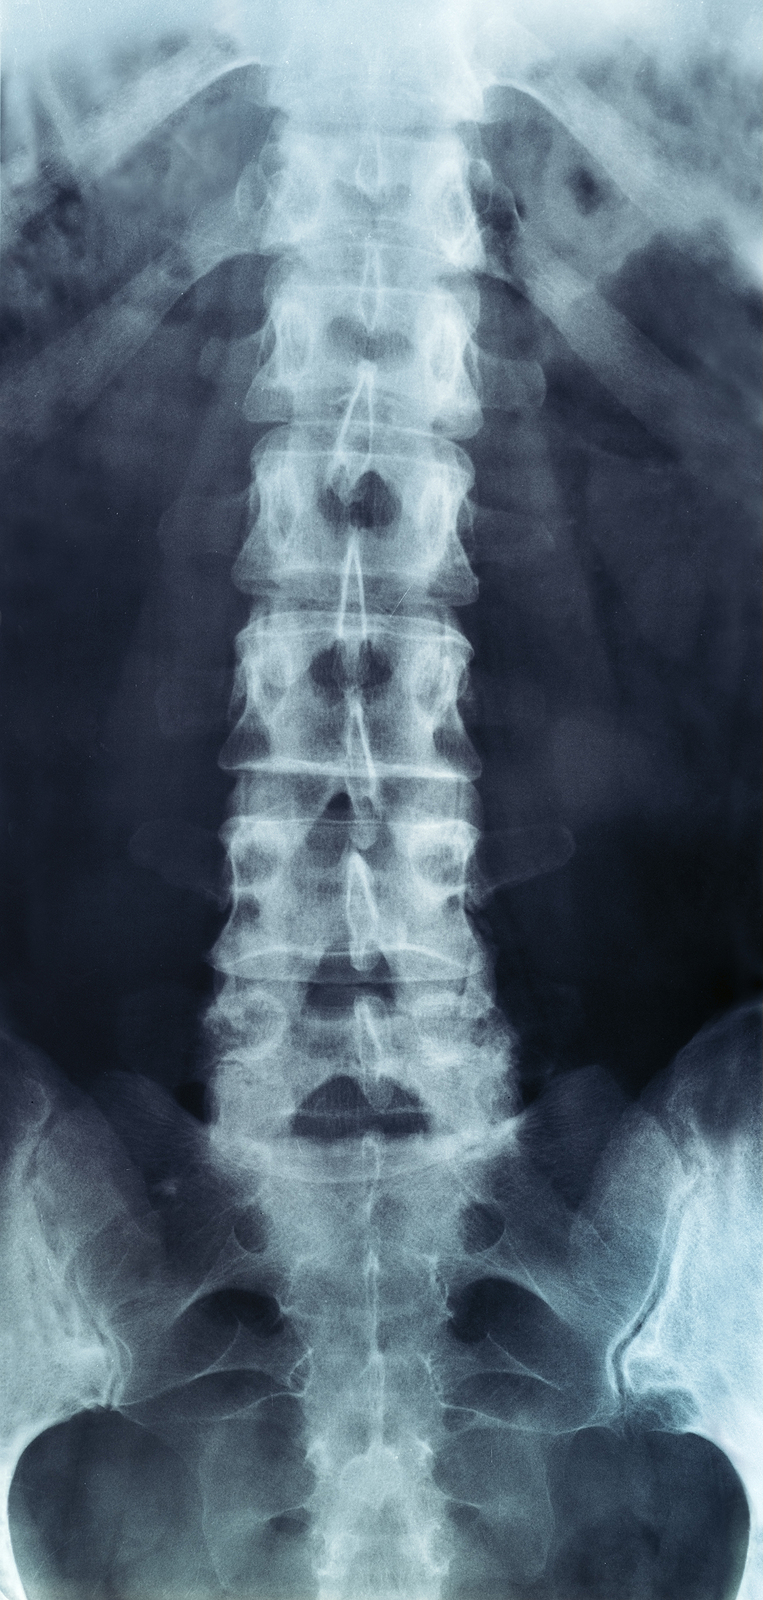

The human spine is made up of 24 spinal bones, called vertebrae, as well as the sacrum and the coccyx. The sacrum is a triangular bone near the bottom of the spine and the coccyx is more commonly known as the tailbone.

Vertebrae are stacked on top of one another to create the spinal column. The spinal column gives the body its form and helps sustain an upright position.

The lumbar spine—where pain is often experienced—is made up of five vertebrae positioned near the bottom of the spinal column. Doctors often refer to these vertebrae as levels L1, L2, L3, L4 and L5. The ‘L’ refers to ‘lumbar’. The lowest vertebra, L5, is connected to the top of the sacrum—a triangular bone at the base of the spine that is located between the two pelvic bones. Some people are born with an extra or sixth lumbar vertebra called L6. Having an extra vertebra doesn't usually cause physical problems.